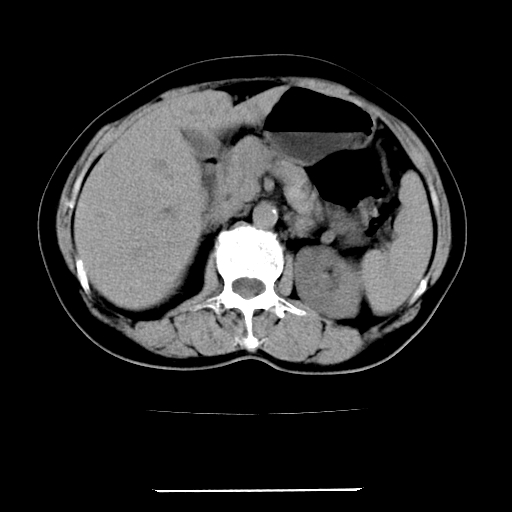

标题: CT22301:女,67岁,上腹部疼痛一周伴皮肤黄染,无发热。 [打印本页]

女,67岁,上腹部疼痛一周伴皮肤黄染,无发热。

左叶肝内胆管结石,并远端肝内胆管扩张。

考虑:肝内胆管结石继发肝内胆管扩张,右肾旋转不良。

肝内外胆管结石并肝内胆管扩张。

建议薄层观察,除外肝门部胆管细胞癌

考虑肝胆管癌;胰头占位?【形态失常,体积增大】

1、肝门高密度影下层面和胰头层面可见轻度胆管扩张,而静脉和延迟期均未见扫描完胰头,不能完全排除胰头占位。2、肝门部高密度影,考虑钙化或结石。

考虑肝门胆管癌伴门脉左支受侵包埋,建议mrcp进一步检查。